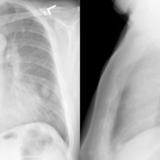

LUL Collapse Case 3 PA

Date: 02/19/2004

Views: 3336

LUL Collapse Case 3 Lateral

Views: 3369